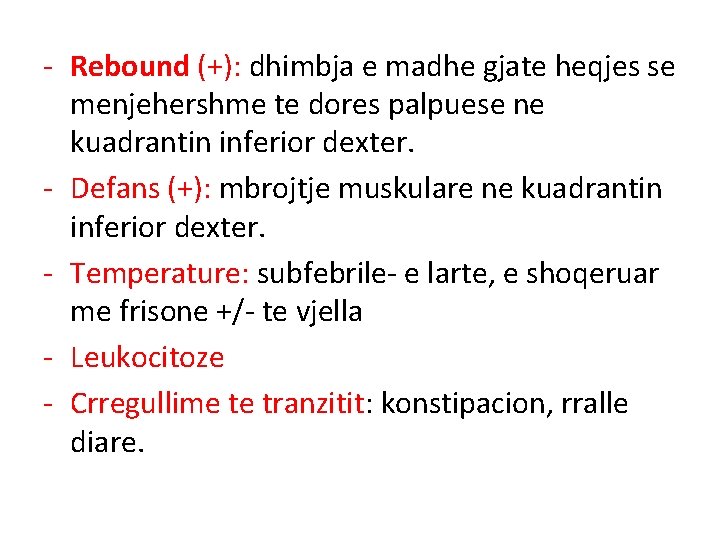

NE PALPIM: - Mac Burney (+): 1/3 e poshtme e distances prej umbilikusit ne spina iliake anteriosuperior

- Rebound (+): dhimbja e madhe gjate heqjes se menjehershme te dores palpuese ne kuadrantin inferior dexter. - Defans (+): mbrojtje muskulare ne kuadrantin inferior dexter. - Temperature: subfebrile- e larte, e shoqeruar me frisone +/- te vjella - Leukocitoze - Crregullime te tranzitit: konstipacion, rralle diare.